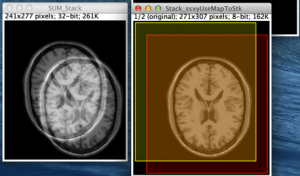

今回は、前回紹介した相互情報量の概念を画像に応用し、実際のMRI画像を用いて相互情報量を計算することにより、画像の類似度を評価してみようと思います。 ①2つの画像の相互情報量を求める 2つの画像A, Bにおける相互情報量とは、前回述べた相互情報量の考え方により、「画像Aの画素値を知ることによって得られる画像Bの画素値についての情報量」ということになります。これはまさに、相互情報量が画像の類似度を表していることを示しています。例えば、2つの画像が全く同じならば、相互情報量は最大になり、2つの画像が全く無関係ならば、相互情報量はゼロになりますね。 簡単のため、2つの画像A, Bの画素値をいずれも ...